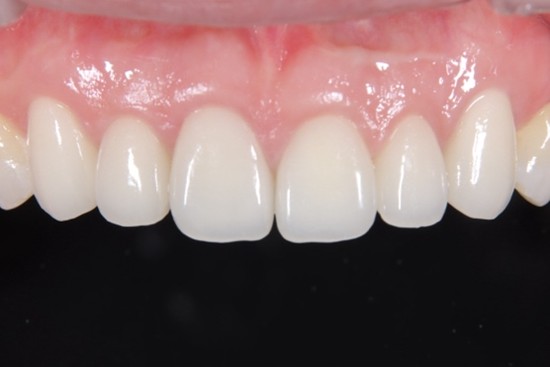

歯周病患者に対して前歯部に審美修復を行ったケースの症例紹介

Before

6前歯の被せ物の歯肉が赤く腫れており膿が出ている部分もあった。審美的とは言えない状況

治療中

セラミック仮着時

After

セラミックセット後3年、歯肉の炎症はなく審美的な結果が得られている

主訴

他院でセラミック矯正を行ったがその後歯肉が腫れてしまい出血する様になった

治療内容

初診時に入っていた被せ物は全て外し仮歯に置き換え、歯周基本治療を行った。その後歯肉の位置を調整して(クラウンレングスニング)仮歯を調整したのちにジルコニアセラミックを作成した。

治療費

90万円

治療期間

9ヶ月

治療回数

15回

想定されたリスク

※歯肉の位置の調整のための手術が必要だったため術後の一時的な腫脹・疼痛があった。

中山亮平先生

戸越なかやま歯科

審美修復に必要なことは、歯肉の健康だとつくづく感じている。いくら被せ物をセラミックで行ったところで土台である歯肉が健康でなければ本当の意味での審美修復は不可能であり長期的な予後が見込めない。まずは炎症のない口腔内の確立を第一に考える必要があると考える。